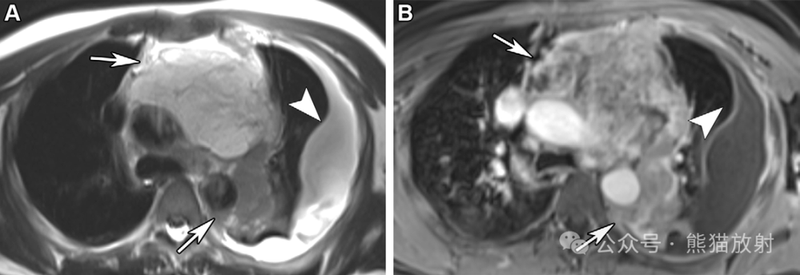

62岁女性,胸膜间皮瘤。(A,B) 轴位 (A) 和冠状 (B) 对比增强胸部 CT 图像显示右侧胸膜肿块(箭),不均质强化,并侵及纵隔和心脏,下腔静脉 (IVC) 血栓形成(B箭头)。(C,D) 下胸部和上腹部的冠状T2WI(C) 和对比增强 (D) MR 图像显示胸膜肿块(箭头)侵及心脏和心内膜,伴瘤栓(白箭头)和血栓 (黑箭头)。MRI有助于评估纵隔和血管的受累情况。